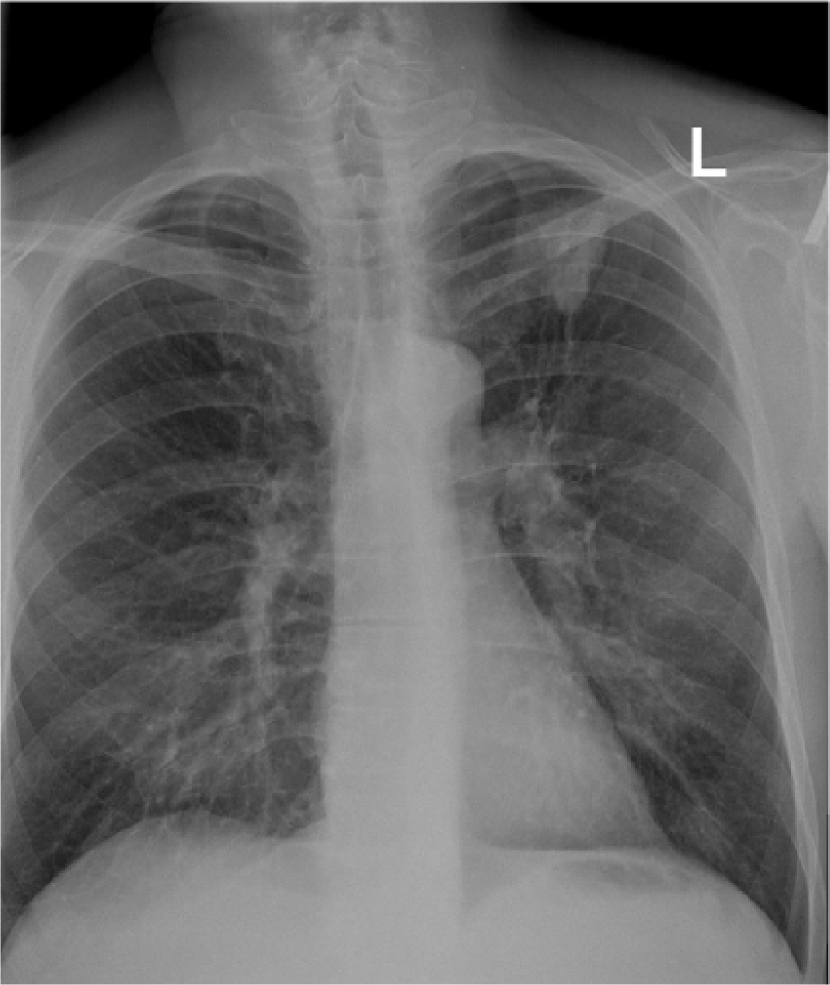

Despite tremendous advancements in tomographic imaging, chest radiography remains the most commonly used imaging modality for pulmonary analysis mainly due to its low cost, low radiation dosage, and widespread availability. Radiation dosage is of particular concern in pediatric applications, especially in neonatal intensive care units where chest radiographs (CXRs) are considered the first option for pulmonary diagnosis [1]. Lung field segmentation is the necessary initial step for image-based pulmonary analysis. Accurate delineation of lung field from CXR, however, is challenging due to ambiguous boundaries, pathologies, occultation of lung field by anatomical structures in thorax, anatomical variation of lung shapes, and size across subjects (Fig. 1). Part of the challenge in developing computer-aided diagnosis (CAD) methods, especially for pediatric cohorts, is also the anatomical shape variation of lung field that occur during growth [2, 3]. As shown in Fig. 1, pediatric cohorts have a more compliant chest wall, small thoracic cage, and relative large abdominal space. Furthermore, the diaphragm of children has smaller apposition area which has a concave shape in the posterior-anterior (PA) view CXR [3]. Therefore, existing approaches to lung field segmentation that are designed primarily for adult cohorts, are not accurate at analyzing the pediatric subjects. Although a few pilot studies such as [2] have been conducted recently to look at the age-related radiological biomarkers in lungs, no comprehensive study of pediatric lung field segmentation exists to the best of our knowledge.

II Datasets and Reference Standards